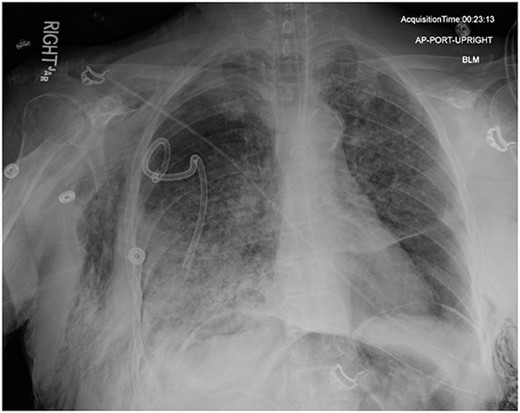

In the operating room (OR), the patient underwent intubation for TBNA using the Monarch® robotic bronchoscopy platform. Nine needle aspirations were obtained from the third-order RLL bronchi with each aliquot subjected to rapid on-site examination. While awaiting results, the patient developed retching, hemoptysis, bronchial bleeding from the superior segment of the RLL lobe and hypotension. The bleeding was managed with ice-cold saline and epinephrine. The patient required aggressive resuscitation with crystalloid, blood products and vasopressor therapy. She was transferred to the ICU where she remained intubated for ongoing resuscitation. In the ICU, the patient developed recurrent hypotension. Chest X-ray (CXR) revealed a right-sided pneumothorax (Fig. 1) that was treated with a small-bore pigtail chest tube and resulted in immediate improvement of her tension physiology. The pneumothorax resolved on repeat chest film while the patient remained intubated and sedated (Fig. 2).

AP upright chest radiograph showing placement of right-sided chest tube and resolution of right pneumothorax.